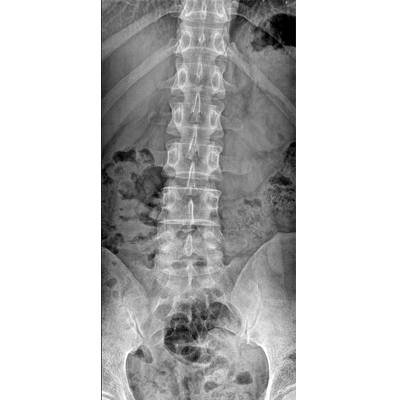

●大尺寸非晶硅平板探測器。

●探測器可以大范圍轉動,大尺寸有效探測面積,可滿足人體多部位攝影需求。